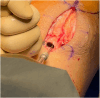

Graft-tunnel mismatch (GTM) is a known technical challenge that can occur with anterior cruciate ligament reconstruction when using a patellar tendon autograft. Two-incision anterior cruciate ligament reconstruction is a well-established technique with excellent outcomes and can serve as an excellent tool to prevent GTM. Traditionally, 2-incision femoral tunnel drilling has been performed using an over-the-top guide through a lateral incision, but more modern retrograde reamer guides can allow this to be done percutaneously. We detail how a minimally invasive 2-incision femoral tunnel drilling technique can be used in patients with patellar tendon lengths that are longer than average to avoid GTM.